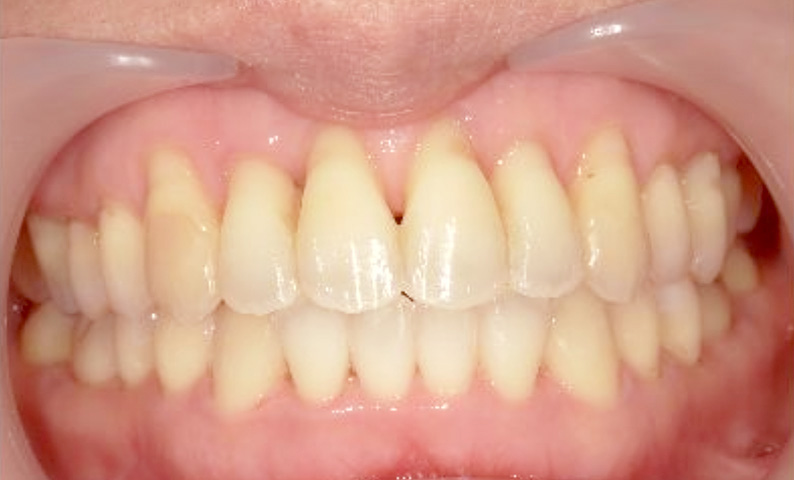

症例_022 上下顎の部分矯正

治療期間:9ヶ月金額:51万円+税女性前歯のガタガタ八重歯

| Before | After |